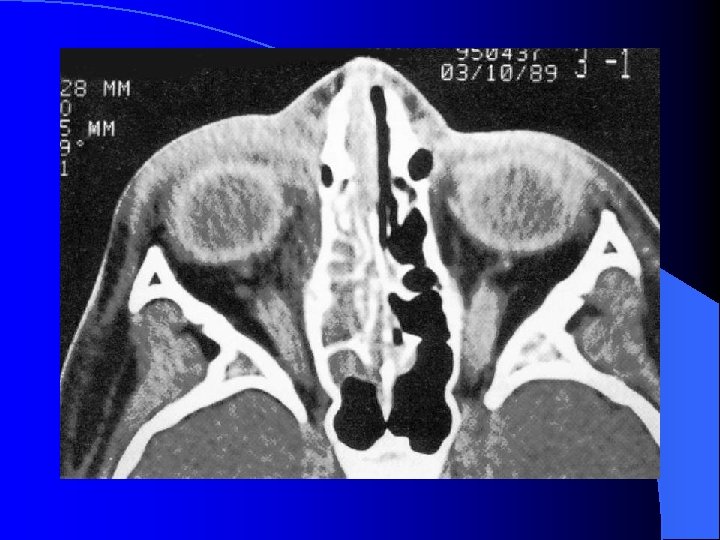

Forme extériorisée = TDM

MALADIES INFECTIEUSES RHINO SINUSIENNES ETHMOIDITE AIGUË IMAGERIE • Radiographie standard • Echo doppler couleur (opérateur dépendant) • TDM sans et avec injection siège, stade collecté, analyse orbitaire fine